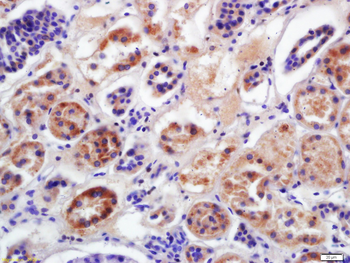

FC, IF, IHC-Fr, IHC-P, WB

应用稀释比例:WB=1:500-2000, IHC-P=1:100-500, IHC-F=1:100-500, IF=1:100-500, Flow-Cyt=1ug/Test